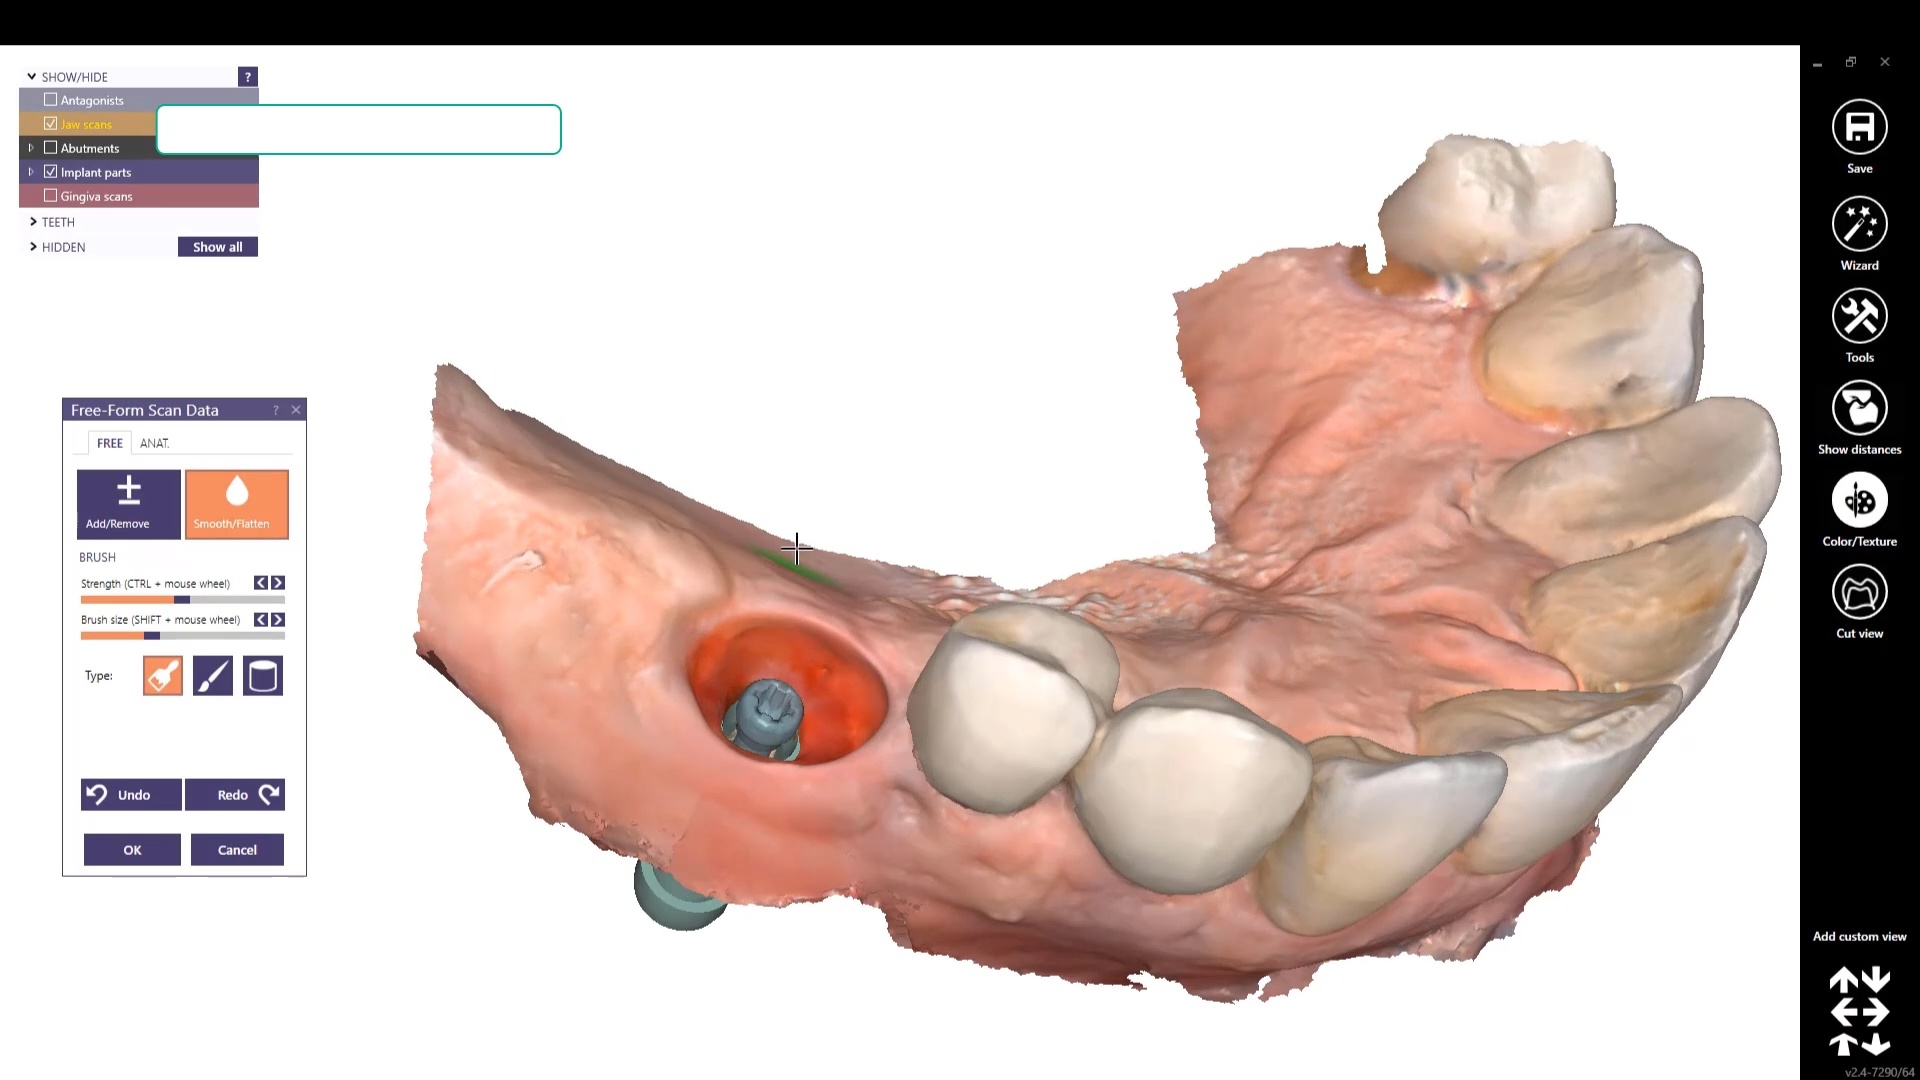

Using the CT as a Remount Jig If You Have Lost The Vertical Dimension For Some Reason or Another

November 20, 2020At CAD-Ray, we have now designed over 20,000 implant cases since 2013. One of the most common requests we get is from doctors doing full arches and their desires to […]